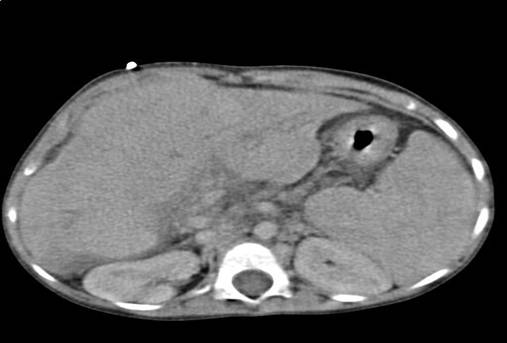

• Компьютерная томография

Более информативный метод, особенно у больных с асцитом и выраженным метеоризмом, который позволяет получить информацию о плотности, гомогенности печёночной ткани; хорошо выявляет даже небольшое количество асцитической жидкости.

Рис. 6. Компьютерная томография печени